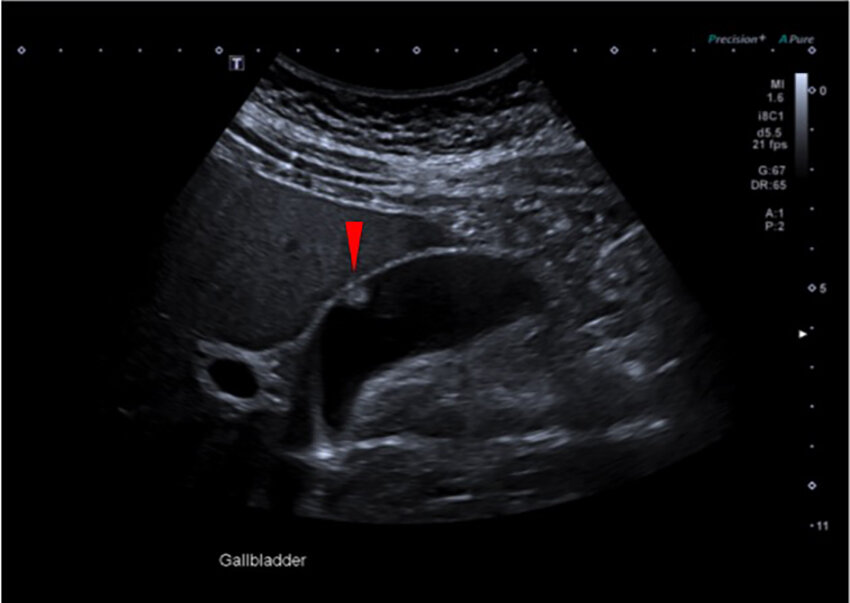

7. kép:

Epehólyag polip.

Epehólyag falának körülírt elváltozása, az epehólyag polip.